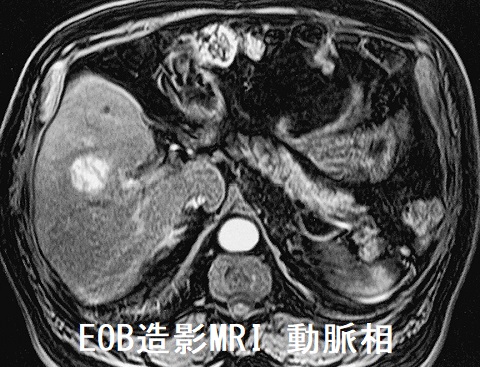

肝血管腫で甲状腺機能低下症

肝血管腫は甲状腺ホルモンを不活化する3型脱ヨード酵素(DIO3)を発現し消費型甲状腺機能低下症に。LT3製剤・LT4製剤で治療。肝細胞癌でも甲状腺機能低下症に。レンビマ®(レンバチニブ)は根治切除不能な分化型甲状腺がん(乳頭癌・濾胞癌)に適応ある分子標的薬で切除不能肝細胞がんに投与すると、甲状腺癌では報告の無かった潜在性甲状腺機能低下症、顕在性甲状腺機能低下症、破壊性甲状腺炎の副作用。甲状腺濾胞癌・濾胞型甲状腺乳頭癌は孤立性肝転移。甲状腺髄様癌・甲状腺カルシトニン陰性神経内分泌腫瘍の肝転移もある。肝膿瘍から甲状腺膿瘍が生じる。